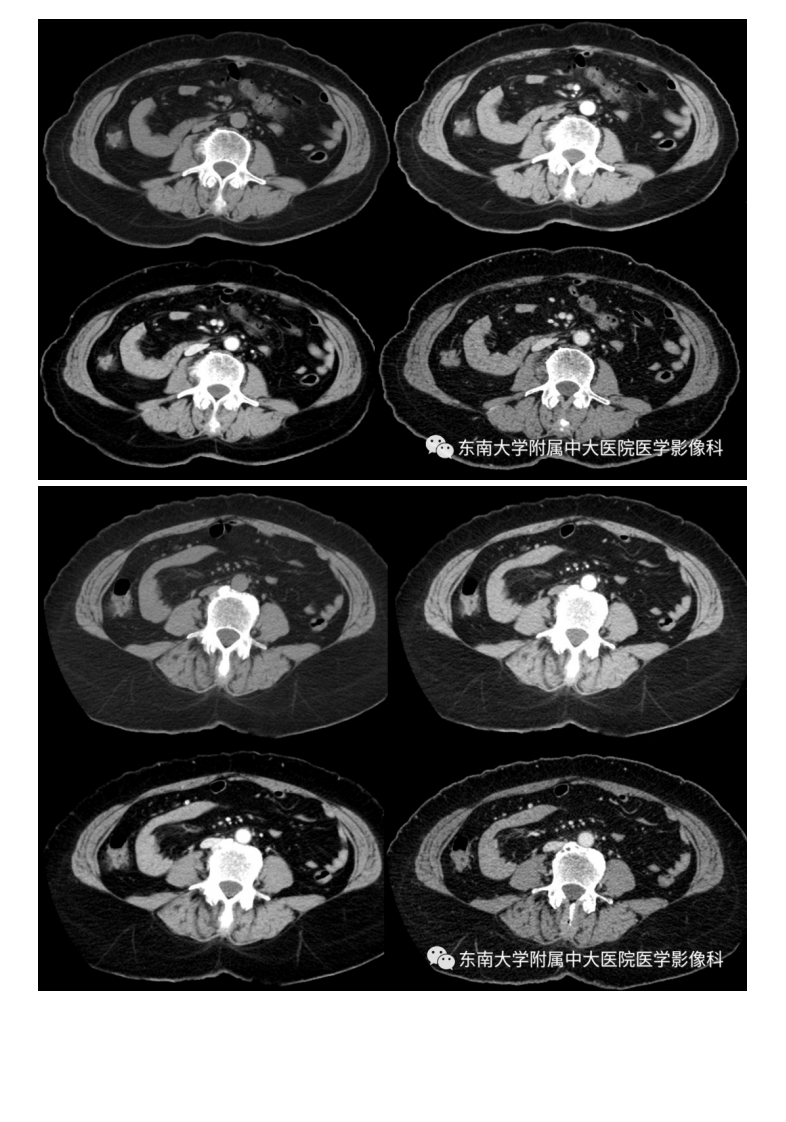

20201014_2【晨读结果公布】2020.10.14消化系统疾病——腹内疝.pdf